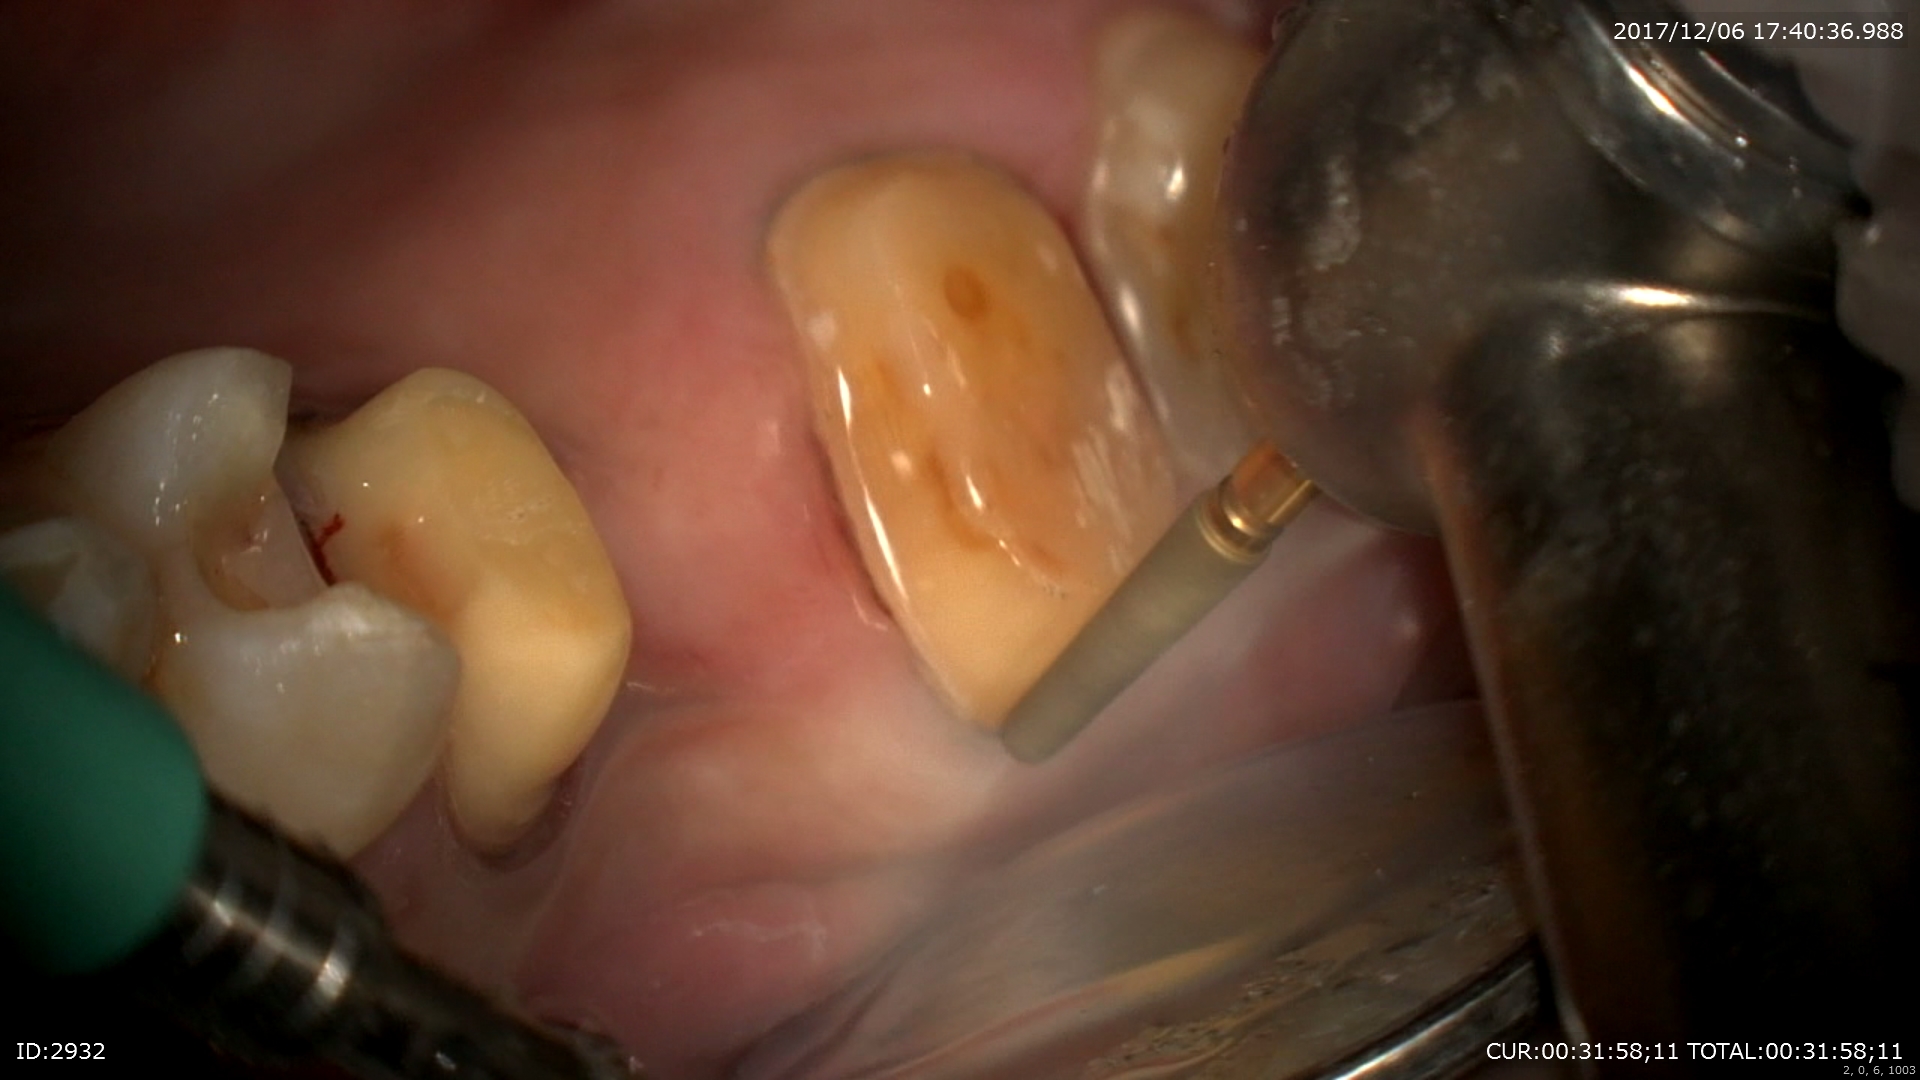

2ケース目:ブリッジの型とり

精密な型取りの為の為、形を整えて。